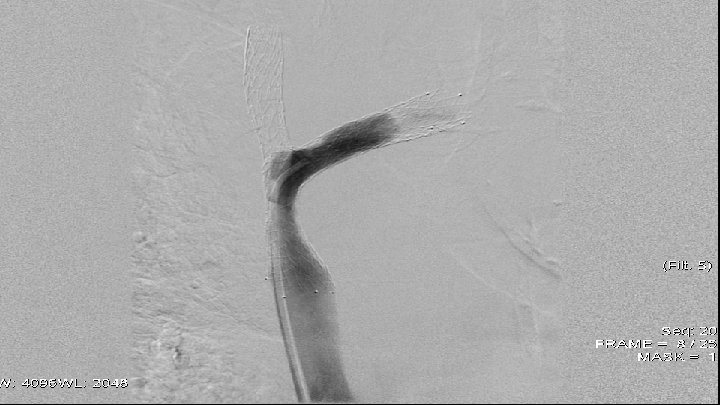

Case 1 q q q 66 y old patient May 2010 – small cell lung cancer was diagnosed April 2011 – venography - high grade stenosis of v. brachiocephalica billateral, PTA and stent implantation of v. brachiocephalica sinstra and baloon angioplasty of v. brachiocephalica dextra July 2011 – CT scan data for restenosis of v. brachiocephalica dextra August 2011 – venography - 90% restenosis of v. brachiocephalica dextra – after predilalatation was implanted stent.